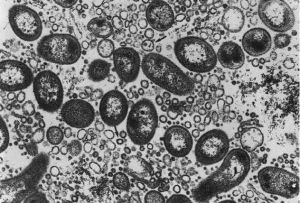

腸炎病菌腸鳴,飧泄,食不化,二曰中氣不足,腸為之苦鳴,三曰邪在大腸,腸中雷鳴,氣上沖胸,;四曰土郁,即《內經》“土郁之發,腸鳴而為數後”,用半夏、木香、茯苓;五曰熱勝,腹中腸鳴,氣上沖胸。《金匱要略》有里寒腸鳴,腹中寒氣,雷鳴切痛,胸脅逆滿嘔吐。李東垣治胃寒泄瀉,腸鳴,用益智、半夏、生薑、大棗。朱丹溪治胃中水火相激腹鳴,用黃芩、黃連、山梔。《張氏醫通·大小府門》謂:肺移寒於腎為“湧水”,其證按腹不堅,水氣客於大腸,疾行則鳴,濯濯如囊裹漿水之病。

當腸內菌群失調,使各種細菌在腸內發酵,產生了大量的氣體,使得胃腸內內容物產生幅度過大,或超出常規的移動,所以就會出現腸鳴。也就是通常所說的腸亢進。